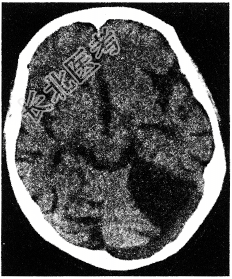

WI出现如图所示脑梗死,该病灶是以下哪两条血管供血区之间边缘带的局部缺血

A、大脑中动脉和大脑前动脉

B、大脑中动脉和大脑后动脉

C、大脑后动脉和小脑上动脉

D、大脑前动脉和大脑后动脉

E、大脑中动脉的深穿支和大脑中动脉的皮质支